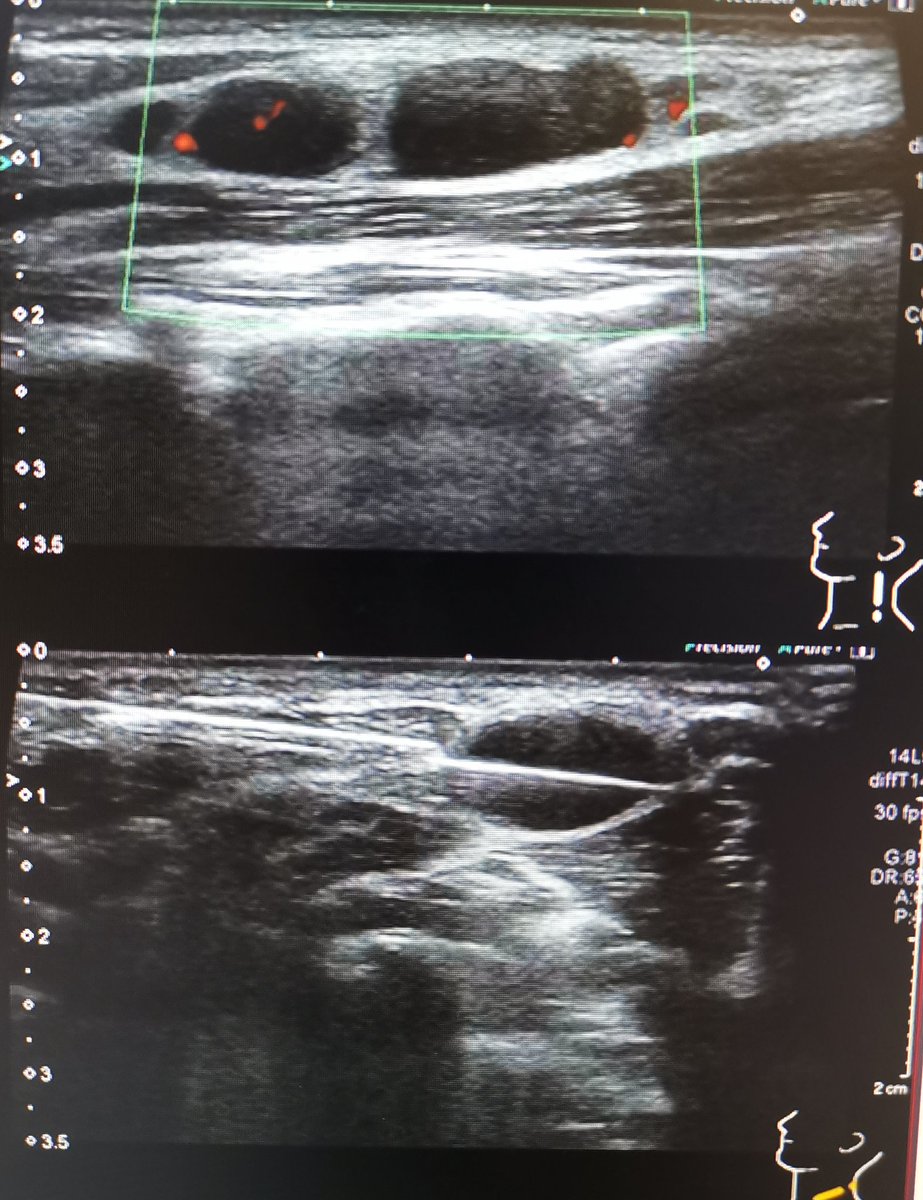

Biopsy proven Kikuchi disease. Not one you see much in the West. Kikuchi-Fukimoto disease = subacute necrotising lymphadenopathy ?autoimmune aetiology. Presents as cervical nodal inflammation. dDx SLE, lymphoma. A self limiting disease.

#radiology#FOAMrad#HNRad#MedEd#kikuchi pic.twitter.com/UzD57wEISZ